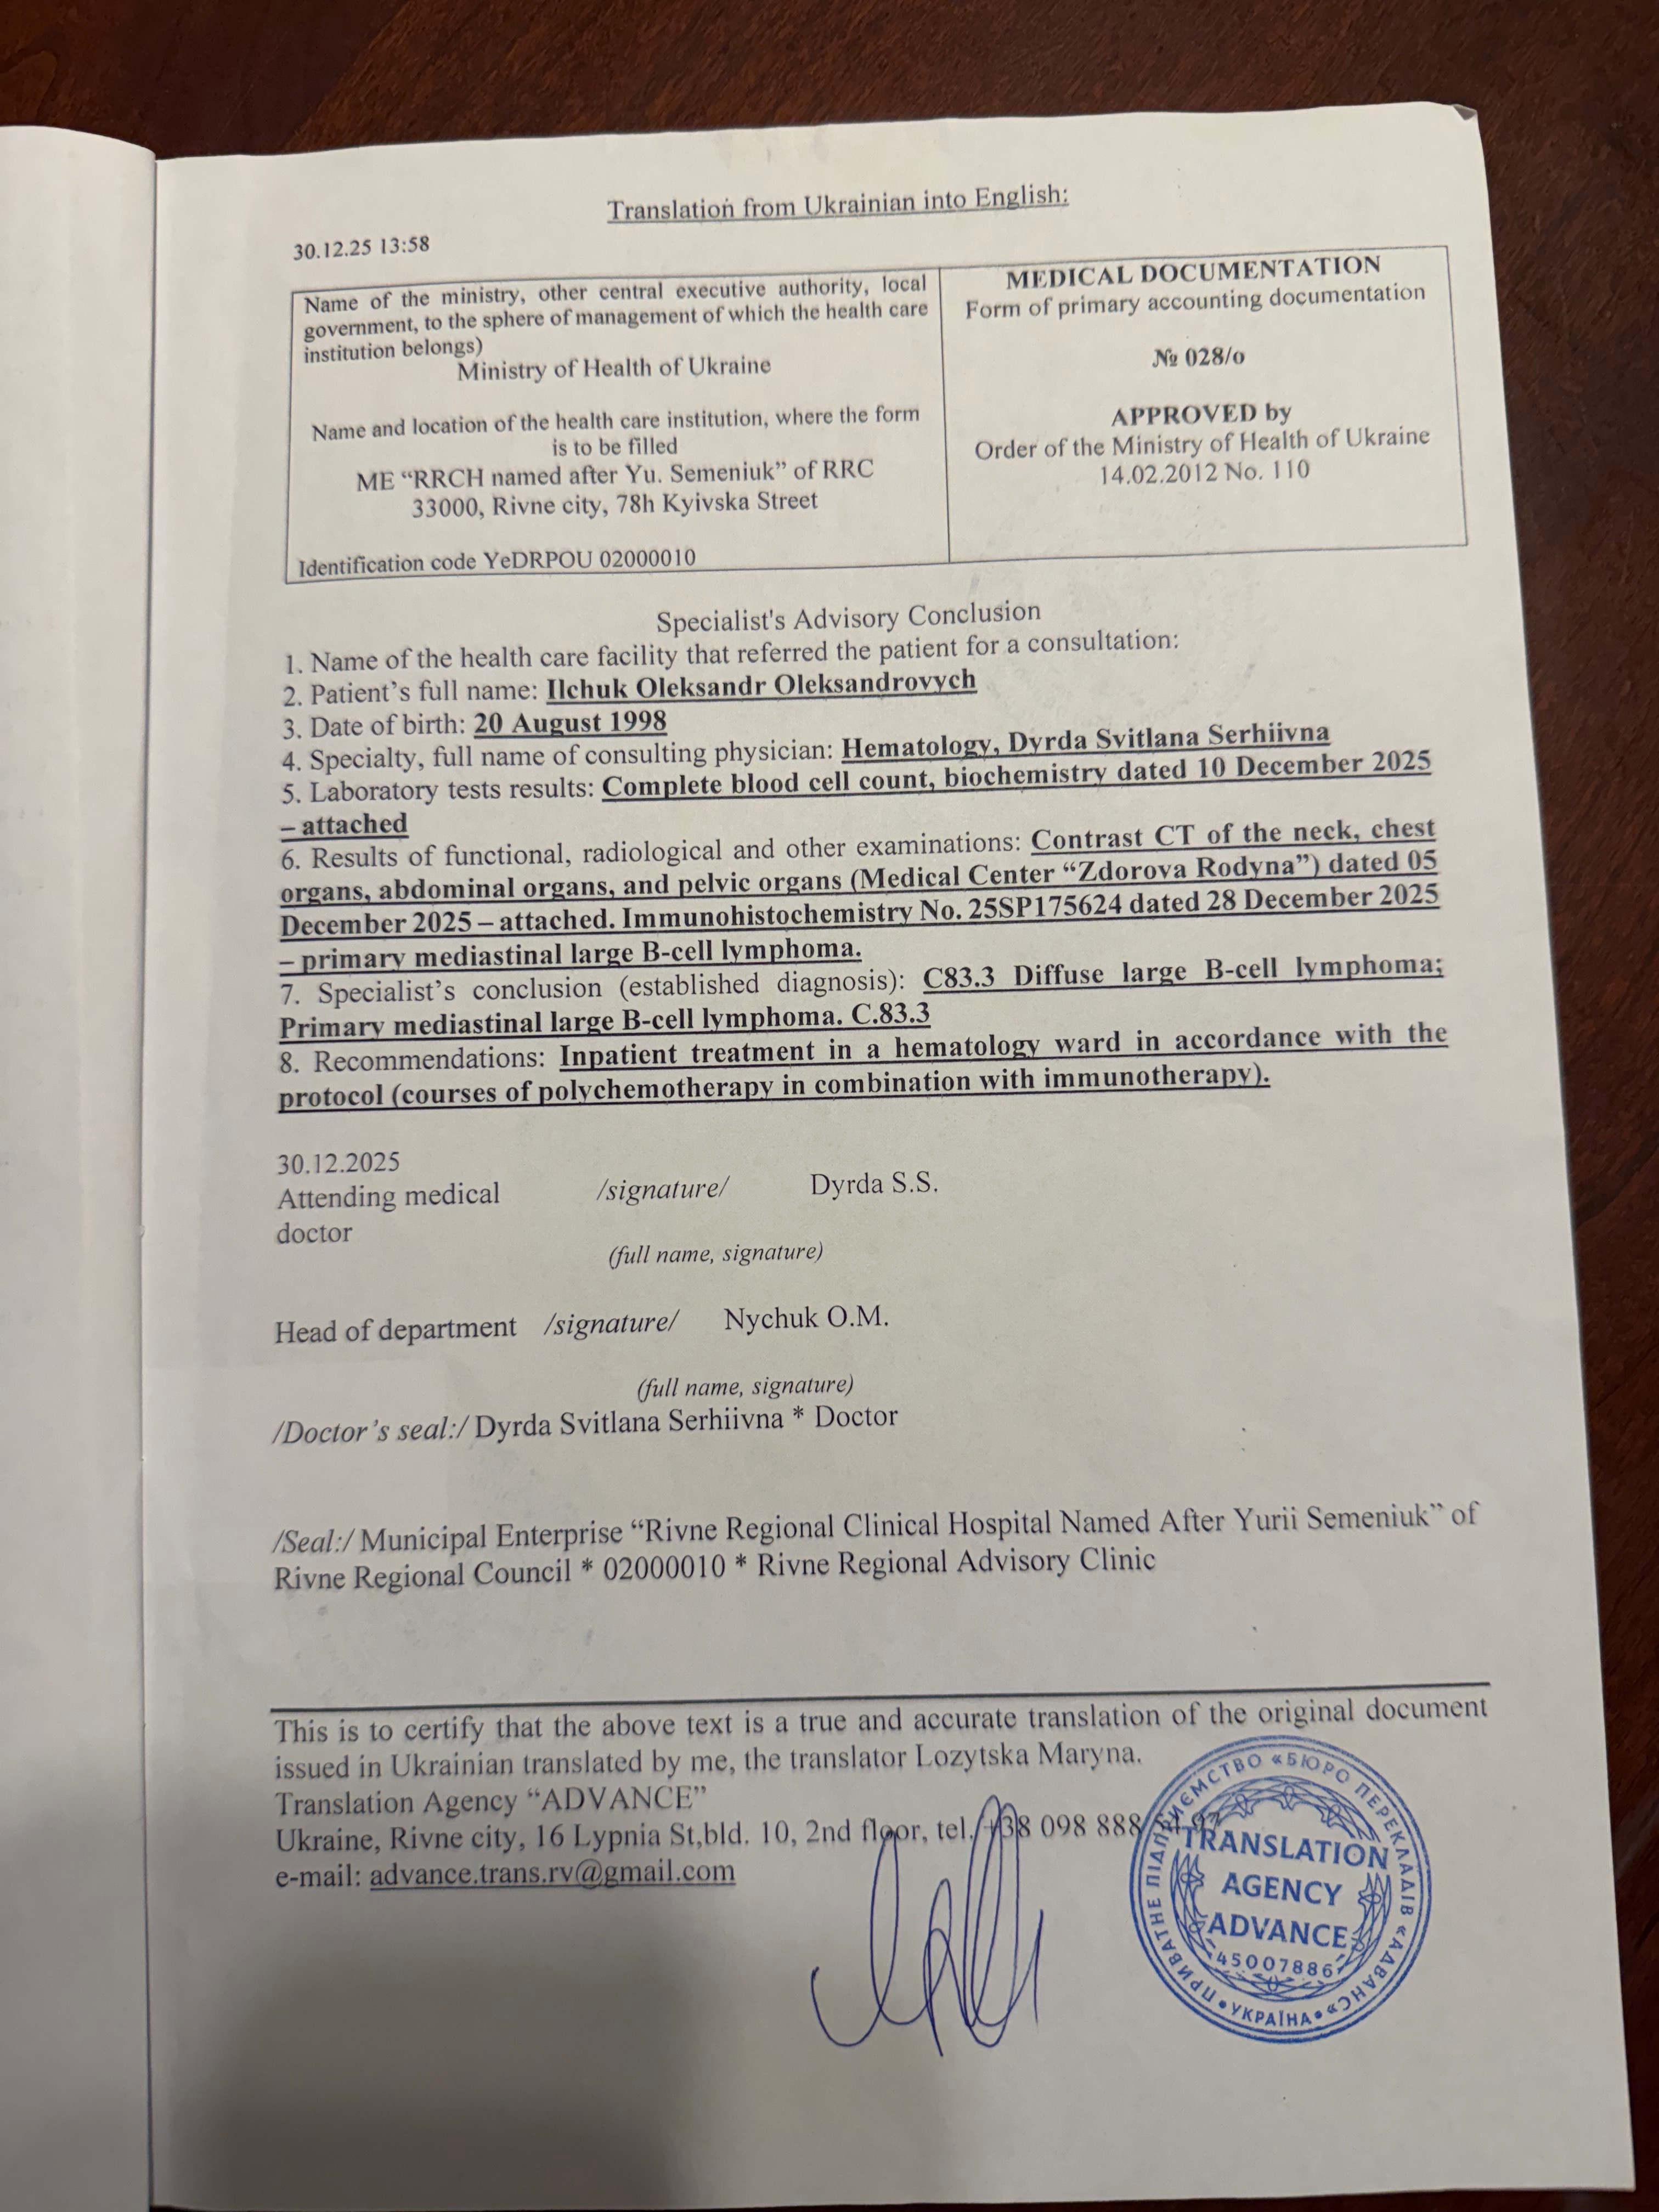

Oleksandr was diagnosed with Primary Mediastinal Large B-Cell Lymphoma, an aggressive but treatable form of cancer. The diagnosis came as a complete shock, especially given his young age and the fact that he was just starting a new chapter of life as a husband and soon-to-be father.

Олександру поставили діагноз — первинна медіастинальна великоклітинна В-клітинна лімфома — агресивна, але лікувальна форма раку. Цей діагноз став повним шоком, особливо з огляду на його молодий вік і те, що він лише починав новий етап життя як чоловік і майбутній батько.